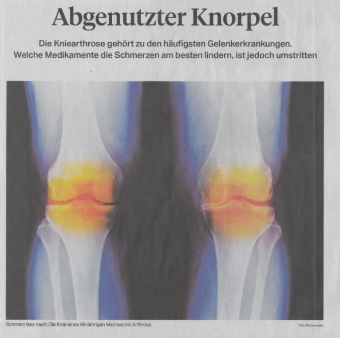

Oberkörper seitliche Ausweichhaltung führt über die Hebelwirkung zu Überbelastung der Knie-Innenseite (Folge Arthrose wird festgestellt?)

Dieses Beispiel: Abgenutzter Knorpel Ursache: Seitliche Oberkörper Ausweichhaltung |

Befindet sich Spannung und Gegenspannung nicht im Gleichgewicht, verzieht es das Skelett. Dadurch verändern sich Knochen- und Gelenkstellungen, was zu einseitiger Überbelastung führt und vielmals als Arthrose betrachtet wird.

Wie kann die Fehlstatik aus Körperteil-Aufnahmen Ursachen bezogen erkannt werden, die zu Knochen-, Gelenk-, Wirbelkörper-, Bandscheiben-Veränderungen führen?

Was kann eine Skelett-Bildaufnahme betreffend die Arthrose aufzeigen?

Wie können so die Fehlstellungen Ursachen bezogen aufgezeigt und behandelt werden?

Körperaufnahmen in Schonhaltung werden Beschwerden sichtbar gemacht, ohne deren Ursachen zu berücksichtigen. Trotz optimaler Bildqualität und hochauflösender Aufnahmen werden die Ursachen der Beschwerden so nicht besser sichtbar, weil eine veränderte Muskelspannung auch eine veränderte Aufnahme zur Folge hat.

So entstehen Beschwerdebilder, bei denen Veränderungen sichtbar werden, ohne den Grund dafür aufzuzeigen.

Dies wiederum führt zu Punktuellen Überbelastungen und wird dann als Abnutzungen, Ablagerungen an Gelenken und Wirbelkörper führen. Was dann z.B. als Arthrose oder Bandscheibenvorfall bebildert wird.

Statt des Beckenausgleiches werden Rückenschmerzen, Hüftbeschwerden und Fehl-Stellungen der Beine und Füsse am Ende einer Fehlbelastungskette behandelt. Die Verspannungslinien führen zu einseitigen Gelenküberbelastungen und werden dann als Arthrose beschrieben und bebildert.